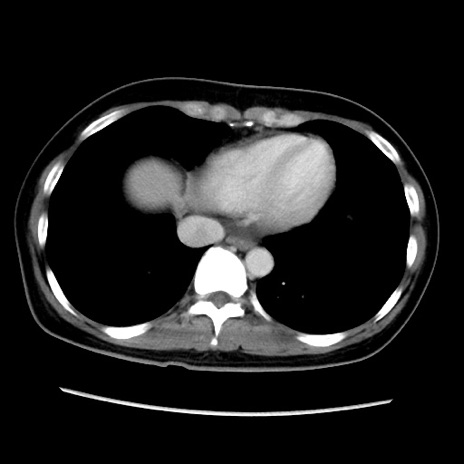

MRI(4日後)

【症例】40歳代女性

【主訴】上下腹部痛

【現病歴】2日目から下腹部痛あり。夜間は痛みで眠れなかった。昨日より上腹部痛と下痢が出現。臥位で痛みは軽快したため、休んでいた。本日になって臥位でも立位でも痛みが強くなってきたため救急要請。

【既往歴】子宮内膜症

【身体所見】部:平坦・軟、左上下腹部に圧痛あり、反跳痛あり。

【データ】WBC 21800、CRP 26.78